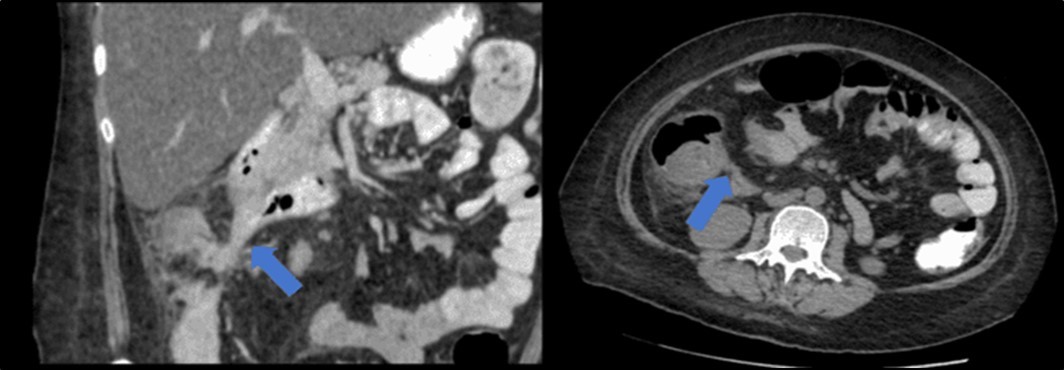

There was no evidence of malignancy or IBD seen during both endoscopic procedures. Computed tomography (CT) scan of the whole abdomen was done which showed inflammatory changes involving the cecum and adjacent duodenum and ileum with coloenteric fistulae. There was noted progression of abdominal lymphadenopathies as well as ascites. Main consideration was an infectious disease process (i.e. TB) (Figure 2, Figure 3, Figure 4 to Figure 5).

Figure 4.Coronal and axial view of the abdomen, the blue arrows pointing towards the suggestive communication to the duodenum